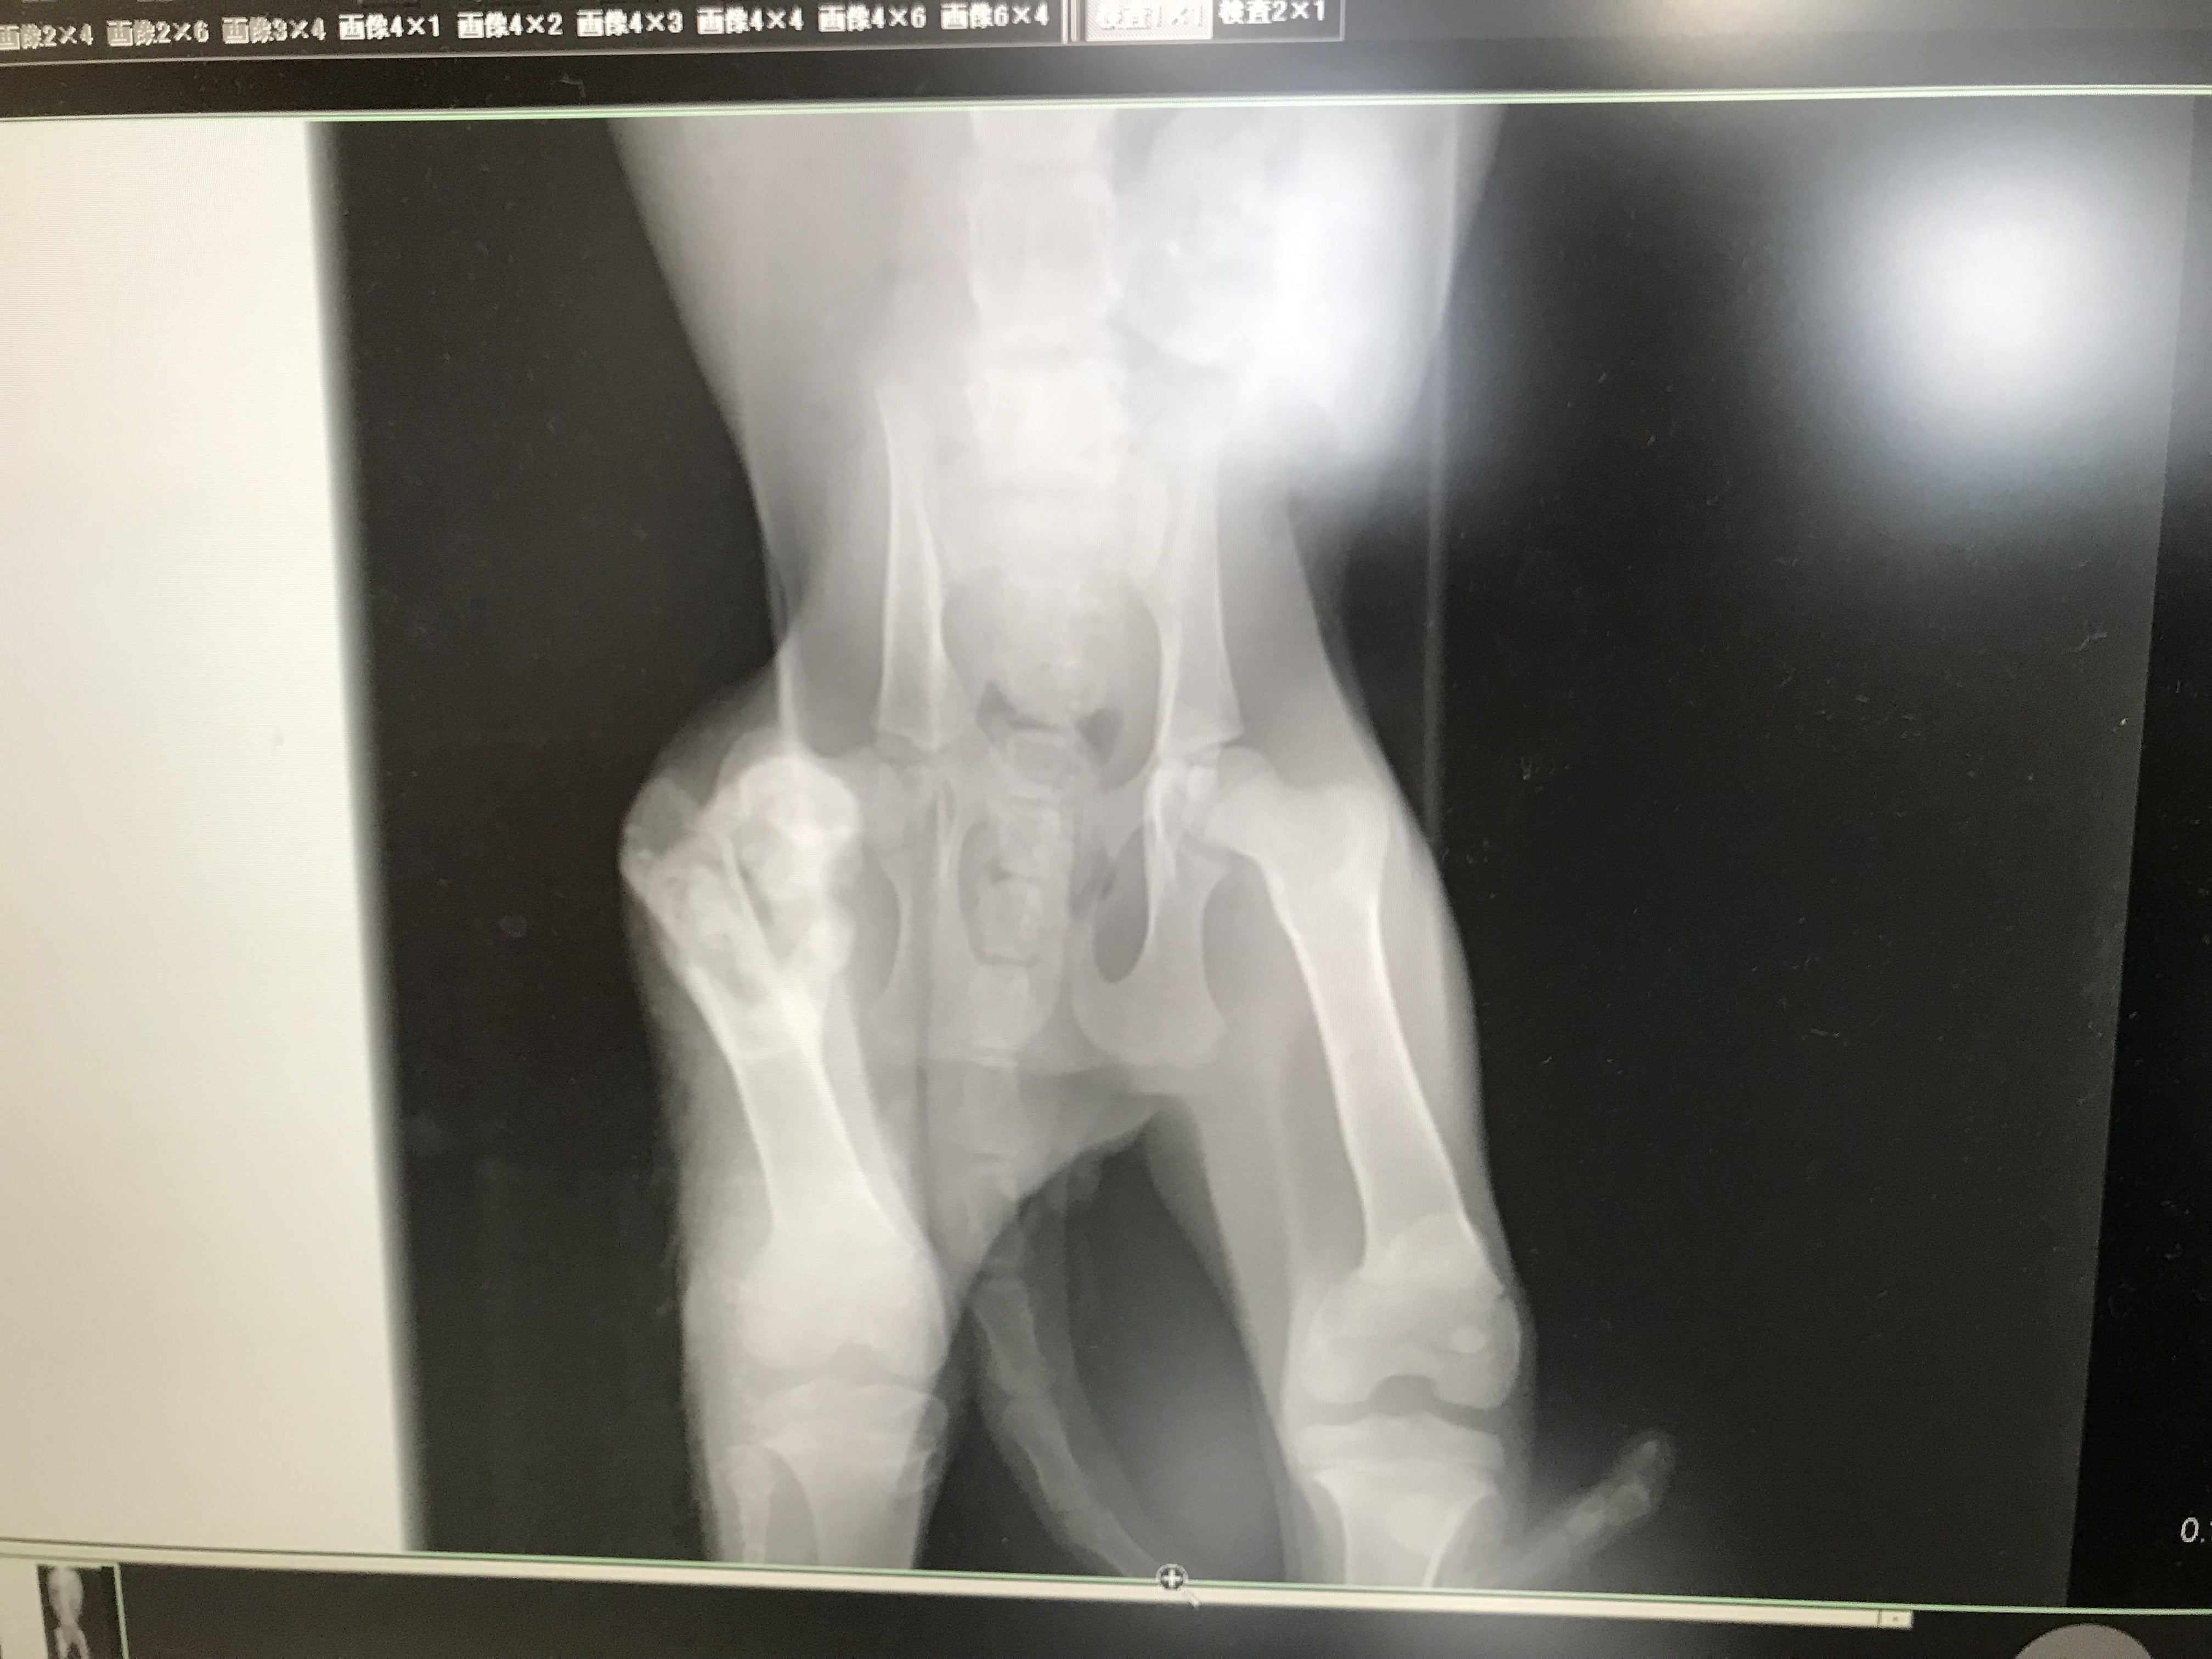

数日前から見かけておりましたが、後ろ右足を引きずっており、日に日に弱っていたため、保護し、動物病院に連れて行きました。

右後ろ足から白いものが見えていたので『ケガして膿んでるのかな』程度と思っておりましたが、先生から伝えられた状況は最悪なもので、白いものは骨が吐出しているもので壊死・炎症を起こしているらしく

まずは炎症があると手術ができない為、飛び出た骨を皮膚の下にもどす。

そして、炎症がおさまってから悪い部分の骨を切りプレートで固定する。

また、9月5日午前中に、体を洗い、骨の消毒、悪い部分を少し削り、皮膚の下へ戻す手術を行いました。

2、炎症を抑えるため骨を削り消毒・皮膚の下へ戻す手術(9月5日実施)

皮膚の下に戻す段階で筋肉で巻いて戻しており、